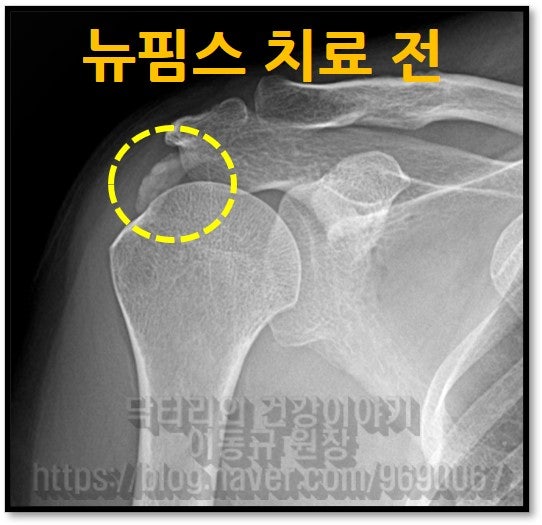

58세 여자 환자분으로 6개월 간 어깨 통증으로 고생을 하신 분입니다. 타병원에서 수차례 주사치료를 받았지만 증상의 호전이 없고 통증이 더 심해지고 가동범위 제한까지 오셨던 분이었습니다. 타병원에서는 수술적 치료를 권유받으셨다고 합니다. 석회성 건염 진단을 받으신 상태로 X-ray 를 확인해 보겠습니다.

이렇게 석회를 분쇄해서 흡입을 하게 되고 뉴핌스치료(석회분쇄흡입술) 후 찍은 X-ray를 보면